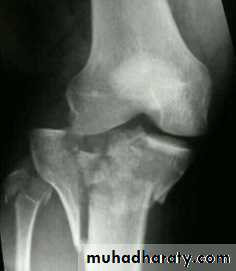

Tibial plateau fractures:Direct blow or fall from height may cause fracture of one tibial condyle or both.

Fracture lateral condyle is the commonest named as bumper fracture

caused by a force that abducts the tibia upon femur while the foot is fixed on ground.Patient usually is an adult, the knee joint is swollen, bruises, there is diffuse tenderness and doughy feel of haemarthrosis.

Imaging : X-ray

: anteroposterior, lateral & oblique views.

CT -Scan may used to detect amount of depression and comminuation.

Tibial plateau fracture

For displaced fractures

treatment is by open reduction and internal fixation with

plate and screws as it is an intra articular fracture.